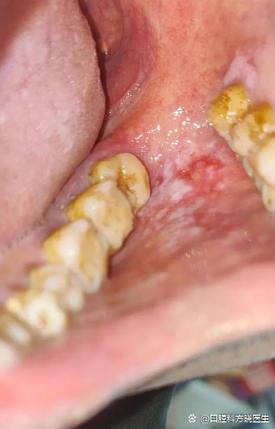

出现非典型性红斑:

- 典型表现: 在白色条纹或斑块的背景上,或者在原本没有病变的区域,出现界限不清、天鹅绒样或颗粒状的红色斑块,这种红色区域不同于正常的黏膜红色,颜色可能更深或更浅,且不均匀。

- 警惕点: 这是癌变过程中非常危险的信号,因为红色区域代表黏膜正在发生异常增生。